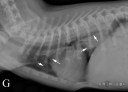

RadioQuiz 18- Réponse